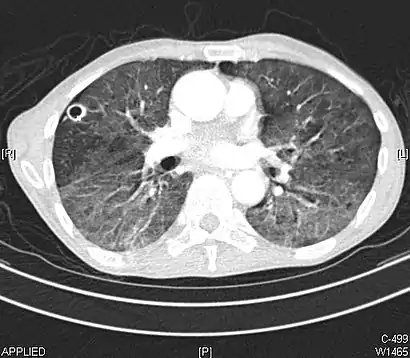

CT image showing diffuse GGOs throughout both lungs. An abscess is also noted in the right lung (screen left). - Adenocarcinoma in situ of the lung